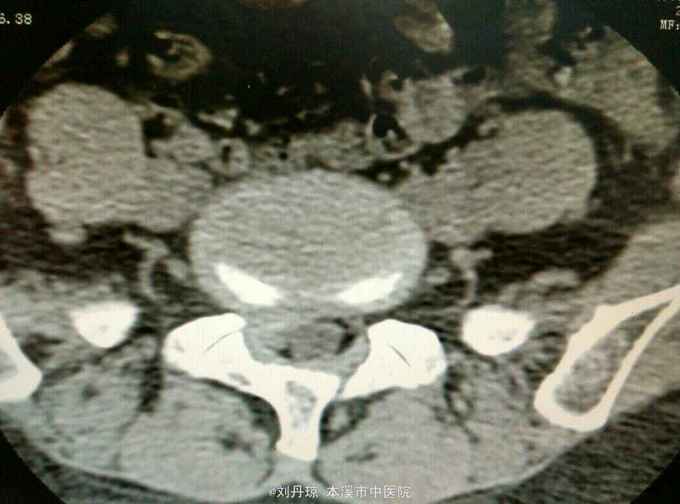

腰痛伴有右下肢放射痛三年,加重十天。患者三年前因抬重物腰部刺痛,休息一周后好转,十天前因开车劳累4.5小时后又洗澡,第2天即感右下肢放射痛难以忍受,遂由门诊收入院治疗。

查体:L5—S1棘突旁压痛阳性。直腿抬高实验。左70度,右30度。加强试验左侧阴性,右侧阳性。腰椎功能障碍。CT:L5—S1椎间盘突出。